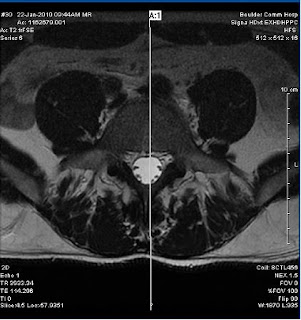

Had my 2 year follow up with MRI and X-ray's last week and I have posted the images below. The surgeon (Dr V) was surprised that the L4 and L5 bones showed signs of improved health ( 2 years ago they both took a beating from the wear and tear on them). The disc is still degenerating but it's seems to have slowed somewhat.

Below are the MRI and X-Ray images:

(MRI courtesy of BCH)